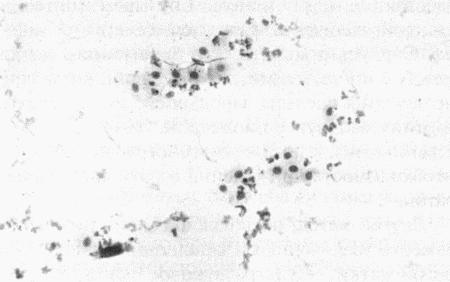

Вагинальная цитология

Повышение концентрации эстрадиола в период проэструса стимулирует деление клеток в базальных слоях вагинального эпителия, но затем концентрация эстрадиола, а соответственно и эндокринная поддержка образования нового, многослойного эпителия снижается, поэтому в образце обнаруживается больше мертвых ороговевших клеток. По мере развития проэструса снижается количество эпителиальных клеток, содержащих ядро. С начала до середины проэструса в вагинальных мазках обнаруживают повышенное содержание эритроцитов. Пик ороговения совпадает с началом повышения концентрации прогестерона; однако в начале эструса исследование не обнаруживает характерных особенностей, которые могли бы указывать на начало фертильного периода. Как правило, такой период наступает несколькими днями позже (табл. 1.1). Тем не менее вагинальная цитология остается популярным методом определения репродуктивного статуса суки из-за своей дешевизны, простоты и доступности. Для получения образца используют ватный тампон, предпочтительно небольшой, который вводят во влагалище и осторожно берут мазок. Полученные клетки помещают под микроскоп, а затем окрашивают контрастным (трихромом) или неконтрастным (например, препаратом Diff-Quik) веществом. При таком окрашивании мертвые кератинизированные клетки становятся оранжевыми, тогда как активные ядерные клетки, а также базальные и парабазальные эпителиальные клетки приобретают различные оттенки от голубого до зеленого.

Ближе к окончанию эструса вагинальные выделения претерпевают характерные изменения (снова выявляются эпителиальные клетки, содержащие ядро, и появляется большое количество лейкоцитов). Такая картина обычно наблюдается через 7–9 дней после пика ЛГ и известна как «вагинальный мазок метэструса». Изменению характера выделений предшествует переходный период, характеризующийся возрастающим количеством активных клеток и указывающий на окончание фертильного периода и эструса (табл. 1.1).

Вагинальная цитология весьма информативна в плане определения фазы эстрального цикла, однако значительные расхождения во времени появления основных признаков эструса по отношению к пику фертильности ограничивает применение указанной методики.

ВАГИНАЛЬНАЯ ЦИТОЛОГИЯ

Вагинальная цитология отражает гормональные изменения, происходящие в организме кошек (фиг. 2.2), особенно в период течки. Данный метод в племенном разведении кошек применяется реже, чем у собак, поскольку процедура может повлиять на ход цикла.

Во время фазы роста фолликулов в выделениях обнаруживаются поверхностные и кератинизированные клетки, наличие которых объясняется воздействием 17-β-эстрадиола. Процентное содержание безъядерных поверхностных клеток возрастает незначительно. В период фолликулярной фазы основной характеристикой вагинальных выделений является медленное сокращение количества клеток, содержащих ядро, промежуточных и базальных клеток. Однако указанные изменения у кошек менее выражены, чем у сук. Наиболее значимым индикатором активности эстрогена является осветление фона на предметном стекле, связанное с резким сокращением обломков разрушенных клеток и слизи. Содержание эозинофилов заметно ниже, чем у собак, эритроциты отсутствуют.

Для интерэструса характерно преимущественное содержание промежуточных клеток с небольшим включением базальных, парабазальных и кератинизированных клеток. В целом именно обломки клеток придают образцу характерный вид.

На стадии анэструса клеток немного, выделения содержат в основном слизь, базальные или парабазальные клетки с редким включением промежуточных клеток. В некоторых случаях присутствуют лейкоциты.

Вагинальная цитология применяется для установления или подтверждения фолликулярной фазы (проэструса или эструса). Обнаружение сперматозоидов вскоре после копуляции позволяет подтвердить факт вязки.

Фиг. 2.2.

Вагинальные выделения кошки (а). Выделения, типичные для фазы эструса. Большая часть клеток представляет собой безъядерные кератинизированные клетки или клетки с пикнотическим ядром. Присутствуют промежуточные клетки (b). Выделения, характерные для метэструса, — «течки», иногда наблюдаемой у кошек в конце эструса. Присутствуют поверхностные и промежуточные клетки, повышено содержание лейкоцитов. Этот короткий метэструс наблюдается в течение 24–48 часов (см. Приложение)